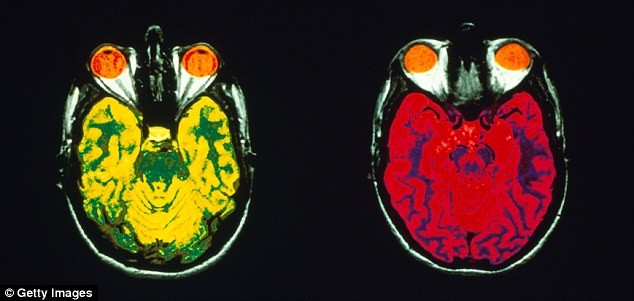

علت عود افسردگی: کوچک شدن نواحی مغزی: تشکیل خاطرات جدید و عواطف در افسردگی مزمن

علت عود افسردگی

نوروسافاری | بر اساس مطالعه ای جدید، اولین علائم افسردگی در نوجوانان و جوانان باید جدی گرفته شود. محققان بین المللی بر لزوم درمان موثر اولین علائم افسردگی به ویژه در نوجوانان و جوانان تاکید می کنند تا از بروز تغییرات مغزی مرتبط با افسردگی شدید پیشگیری شود.   به گزارش …